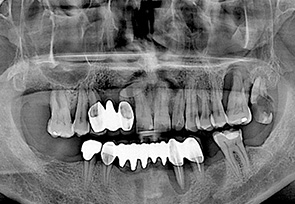

before

after